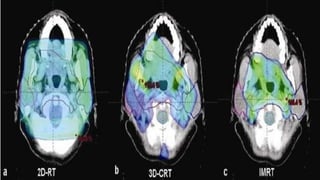

CONVENTIONAL VS 3D – CRT VS IMRT

• Conventional Radiotherapy

1) Uses a number of coplanar beams.

2) Beam shaping by using customized blocks.

3) Use of wedges for producing desired dose distribution.

• 3D – Conformal Radiotherapy

1) Uses 3D planning techniques & special delivery systems to shape the fields – to reduce normal tissue

damage close to the target volume.

2) Uses a larger number of beams.

3) Beam shaping done by MLC s.

• Intensity Modulated Radiotherapy

1) Large number of beams are used from different directions.

2) Each beam divided into number of beamlets whose intensity can be modulated.

3) Intensity modulation & beam shaping done by MLC s.